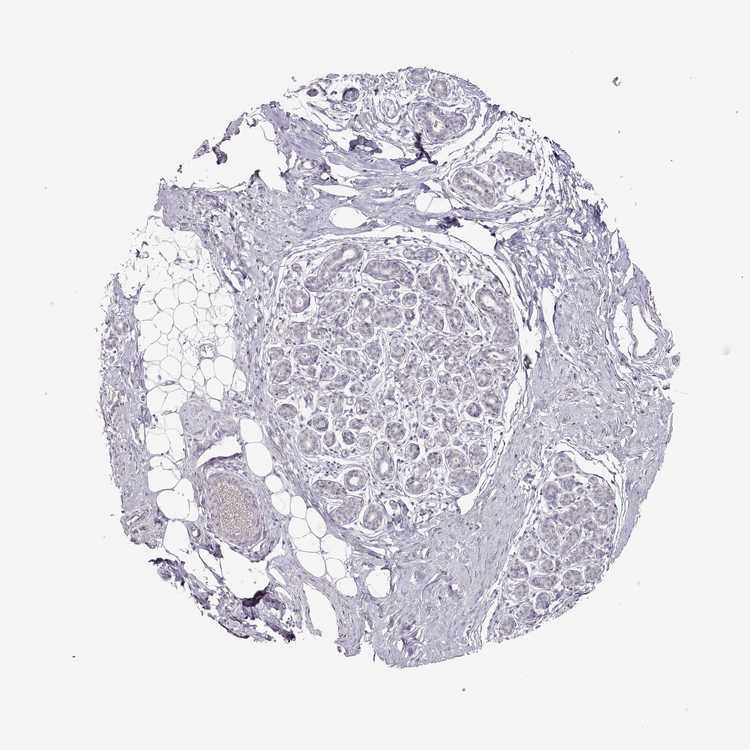

BREAST - Antibody stainingi

Antibody staining in the annotated cell types in the current human tissue is reported as not detected, low, medium, or high, based on conventional immunohistochemistry profiling in selected tissues. This score is based on the combination of the staining intensity and fraction of stained cells.

Each image is clickable and will lead to virtual microscopy that enables deeper exploration of all samples and also displays staining intensity scores, fraction scores and subcellular localization as well as patient and tissue information for each sample.

Antibody HPA049627

Adipocytes Not detected

Glandular cells Not detected

Myoepithelial cells Not detected